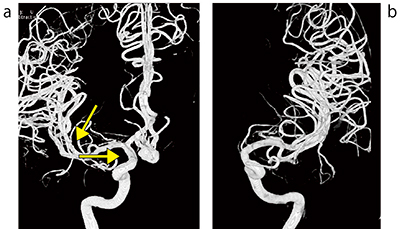

手術前の血管造影(右内頸動脈撮影)にて最大径10.7mm・ネック5.53mmの未破裂前交通動脈瘤を認めた(図4 a)。右前頭側頭開頭にて開頭クリッピング術を施行した。

手術ではチタン製クリップを4つ使用したため,手術後の頭部CTにて強い金属アーチファクトを認めた。頭部3D-CTAは金属アーチファクトが強く発生すると予測し,fusionとO-MARを併用した。頭部3D-CTAのFBP VR画像は右内頸動脈の描出は良好であるが,右中大脳動脈が一部欠損している(図5 a)。O-MAR VR画像は,右中大脳動脈の描出は良好であるが,右内頸動脈が描出不良である(図5 b)。fusion VR画像(図5 c)は右中大脳動脈・右内頸動脈とも描出良好であり,手術前の3D-DSA(図4 a)とほぼ同じ血管描出となっているのが確認できる。

図4 症例:未破裂前交通動脈瘤

a:手術前3D-DSA 右内頸動脈撮影

b:手術前3D-DSA 左内頸動脈撮影